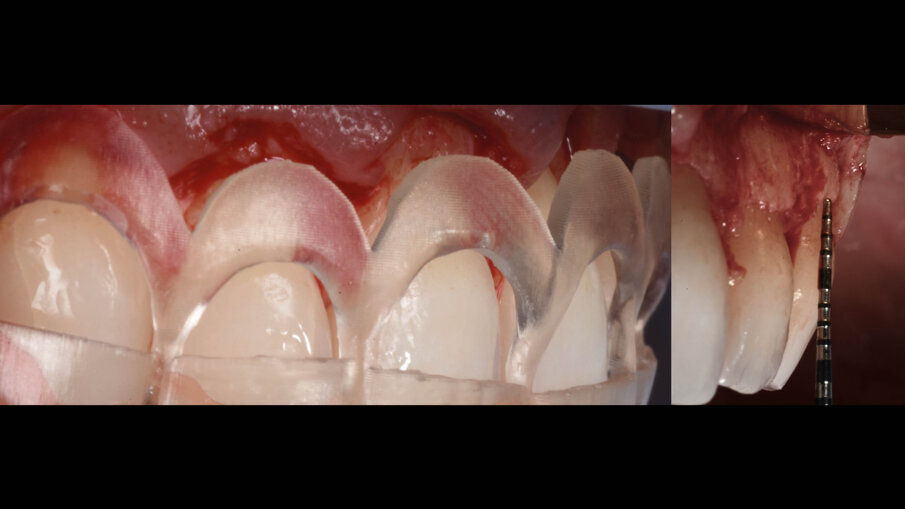

È perciò possibile durante la procedura di allungamento di corona clinica eseguire foto e video con un paziente completamente cooperativo. La prima procedura è la gengivectomia che ha lo scopo di eliminare la gengiva in eccesso e di esporre lo smalto dei denti altresì nascosto (Fig. 12). Una volta completata questa procedura si procede all’elevazione di un lembo a tutto spessore vestibolare che si estende per tutta la zona interessata dalla procedura. La mascherina chirurgica viene a questo punto ri-inserita in bocca per poter assistere la resezione della quantità di osso indicata per correggere la dimensione della zona di attacco sopra crestale (Fig. 13) La chirurgia ossea resettiva viene eseguita con l’ausilio di frese diamantate a palla con diverse dimensioni per le zone vestibolari e interprossimali oppure con strumenti piezo-elettrici. A procedura ultimata si può vedere come la nuova anatomia sia più consona all’attacco dei tessuti molli e favorente una miglior salute dell’attacco dento parodontale (Fig. 14).

Fig. 12_Esposizione dello smalto dopo la gengivectomia.

Fig. 13_La guida favorisce la chirurgia ossea resettiva.